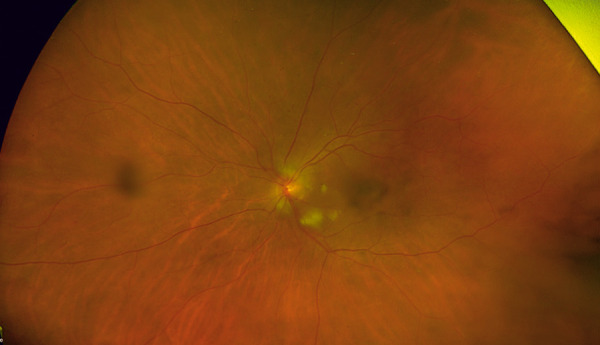

Observations: We report two cases of ophthalmic calciphylaxis presenting as (1) anterior ischemic optic neuropathy (AION) and cilioretinal artery occlusion in a 76-year-old woman with pre-dialysis kidney failure, and (2) AION with contralateral central retinal artery occlusion (CRAO) in a 44-year-old man on hemodialysis.